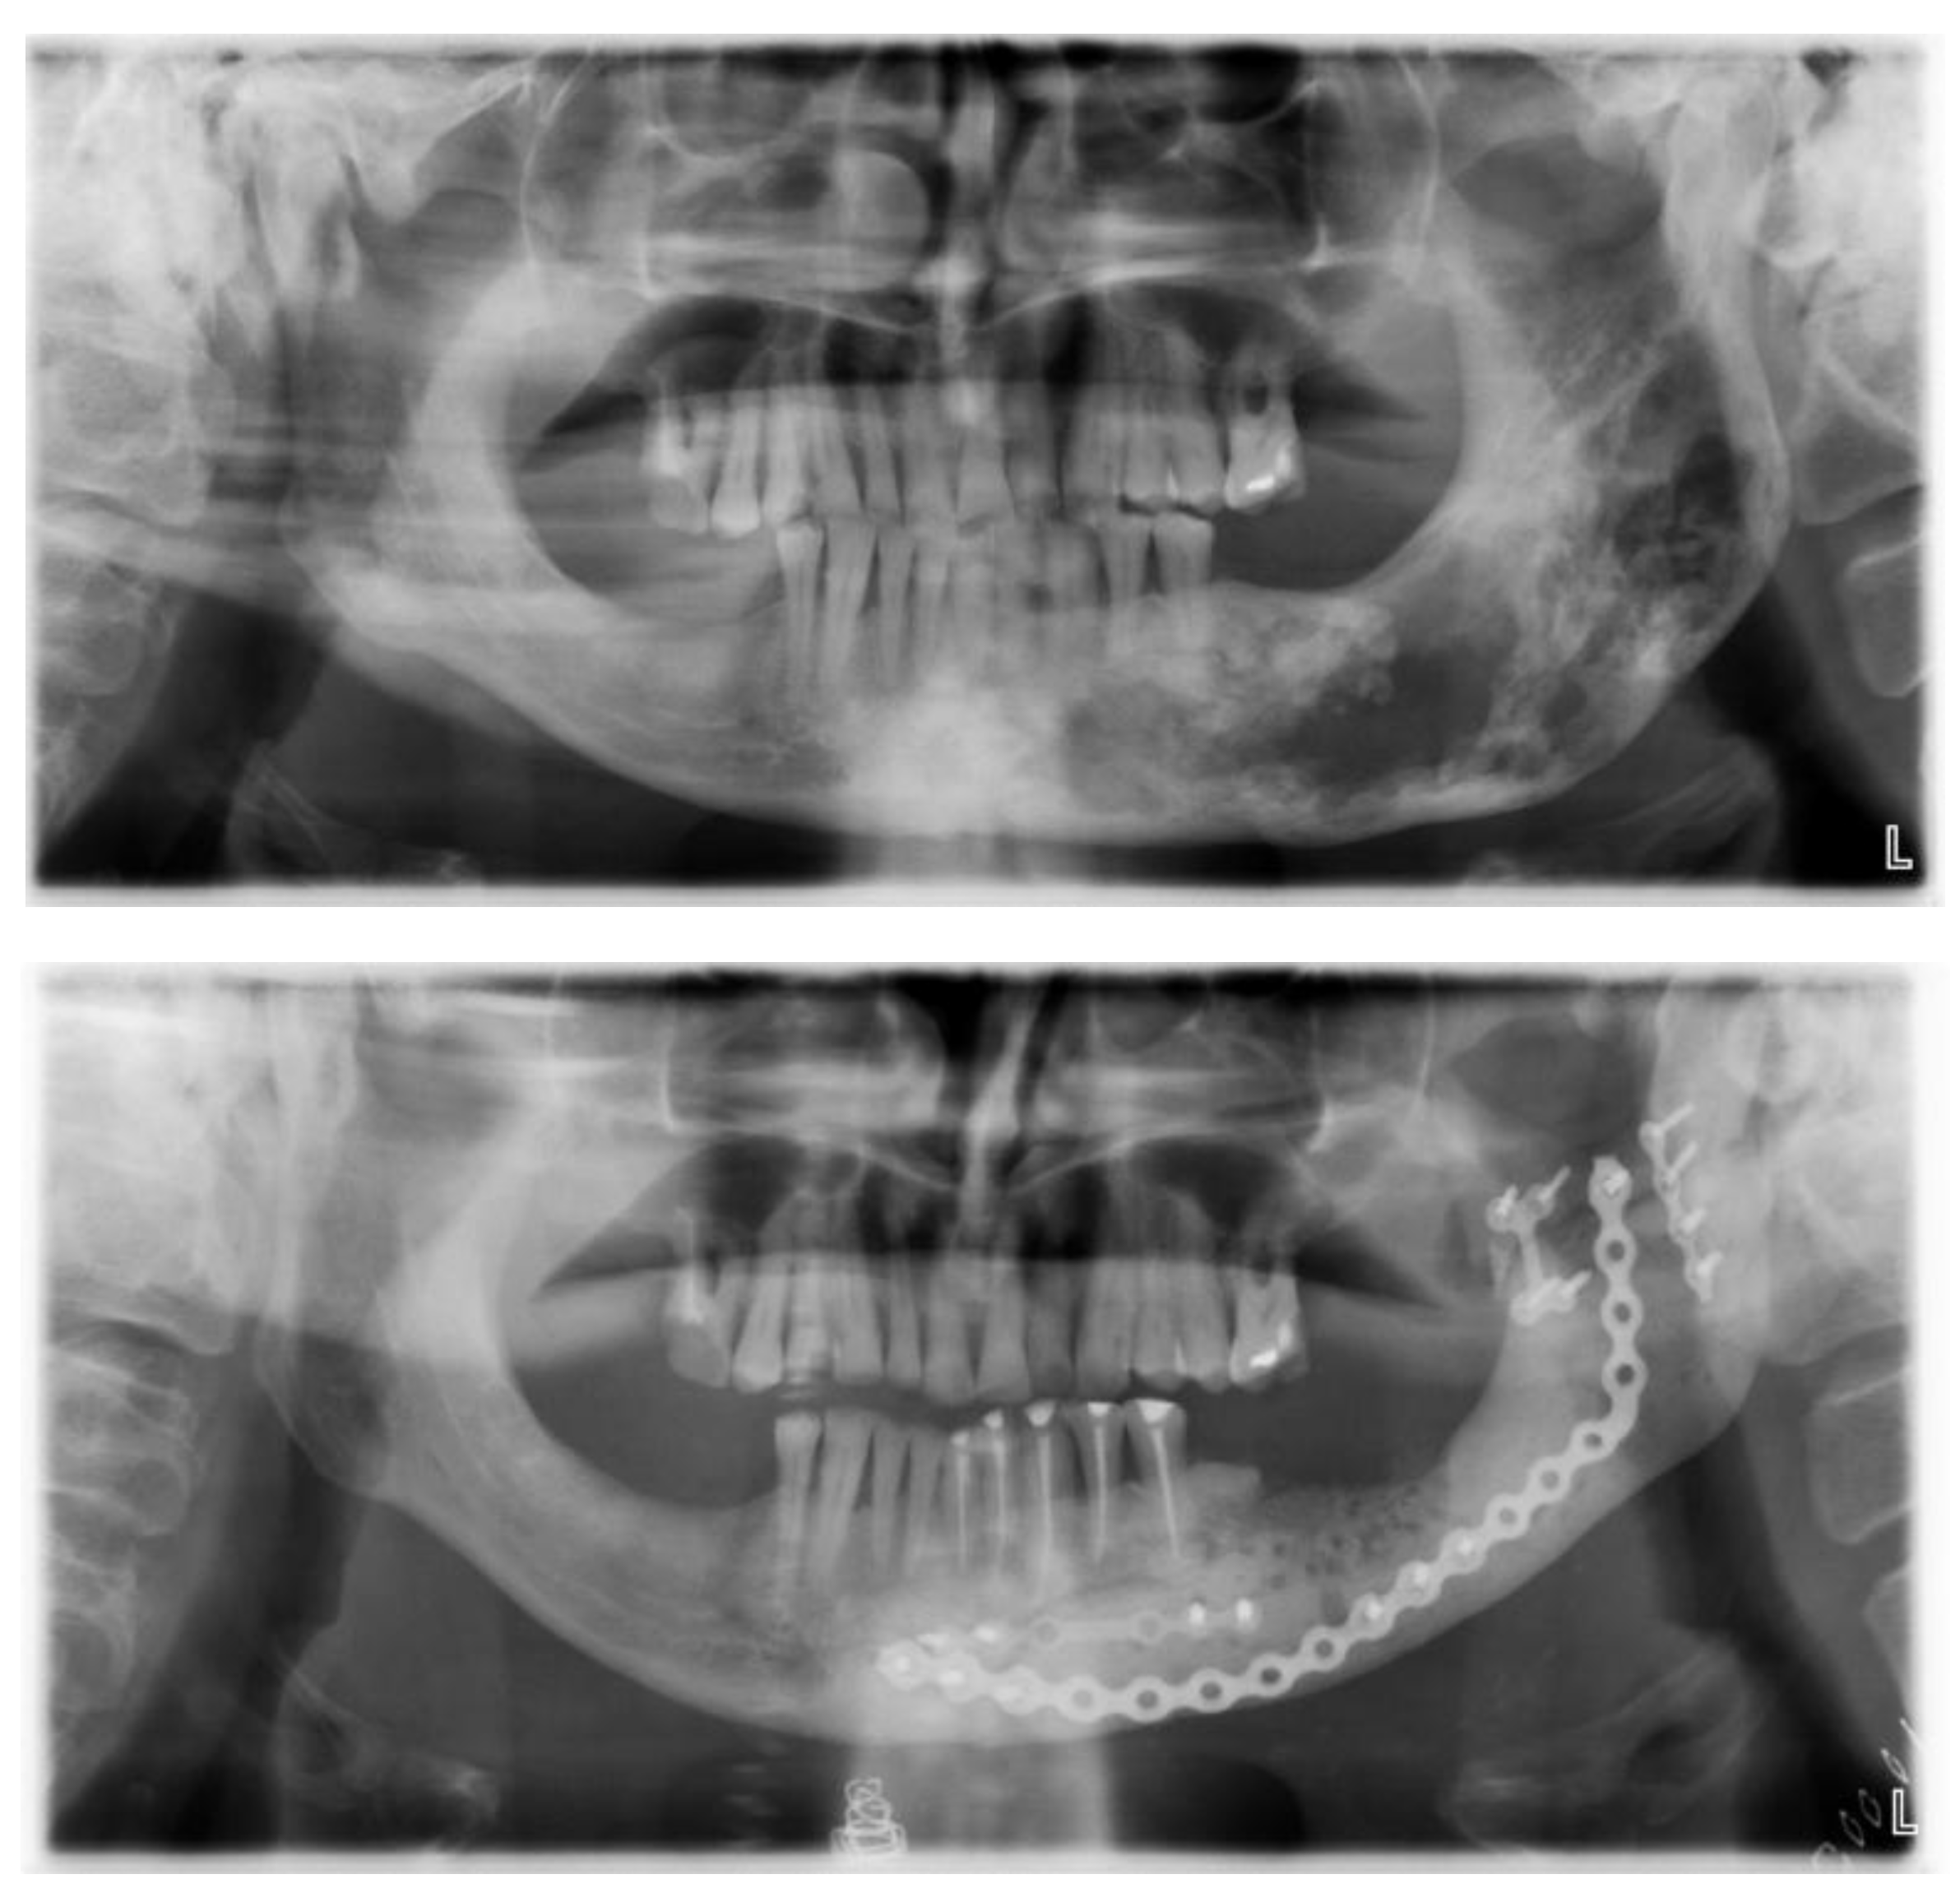

- phase 1: Conversion of the CT scan of the mandible from DICOM format to a 3D STL model

- phase 2: Model of the deformed part of the mandible before and after computer-assisted resection